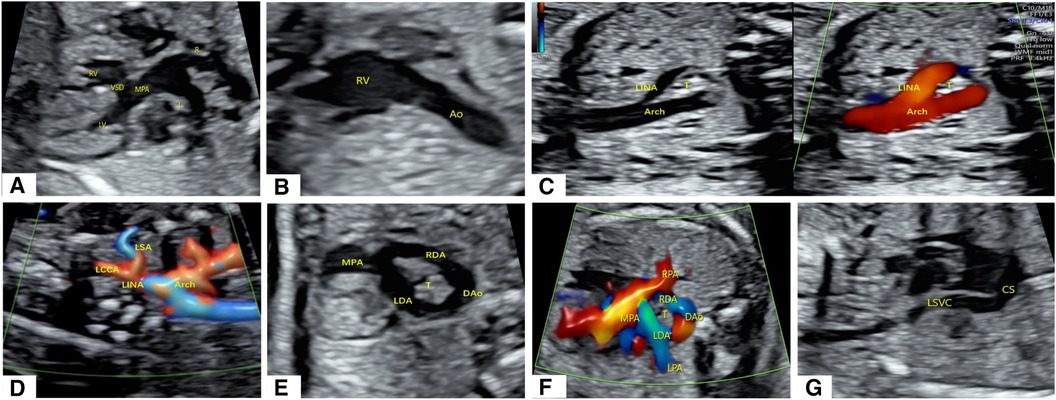

To better visualize the spatial effect, we used a four-dimensional (4D) color Doppler with spatiotemporal image correlation (STIC) HD live flow mode (Voluson E10, GE Healthcare, Zipf, Austria) to clearly display ventricular arterial connectivity and the direction of vessel travel. From this three-dimensional (3D) image, it can be inferred that in the d-TGA, the RAA with LDA formed a “U”-shaped vascular ring. At this point, the RDA was located immediately below the RAA and could only be observed with flickering of the RDA in certain cardiac cycles (Figure 2A, Supplementary Video S2).

Figure 2. Cardiovascular abnormalities of this fetus observed using the STIC HD live flow mode and embryonic development patterns based on Edward's double aortic arch system theory. (A) Shown from the anterior view, we used STIC HD live flow mode to observe that the first blood vessel originating from the ascending aorta was the LINA, which then separates into the LCCA and LSA, followed by the RCCA and RSA (*indicates the “O”-shaped vascular ring, ** indicates red blood flow indicates the RDA). (B) Shown from the posterior view, we used STIC HD live flow Silhouette mode to find the RDA (*indicates the “O”-shaped vascular ring). (C) Embryonic development patterns based on Edward's double aortic arch system theory.

Furthermore, we utilized the STIC HD live flow Silhouette mode (CFM Silhou.90, CFM thresh.30, Transp. CFM 20) to identify the RDA hidden beneath the RAA via a posterior view, which required adjustments in the image quality and angle when applying STIC. The LDA and RDA originated from the proximal end of the LPA and RPA, respectively, and converged into the DAo. Different blood flow directions could help distinguish between pulmonary arteries and veins. Due to angle factors, only the first branch of the Ao could be seen (Figure 2B, Supplementary Video S3). Following multidisciplinary counseling and discussions with her family, this female patient decided to terminate her pregnancy and refused to undergo genetic testing.